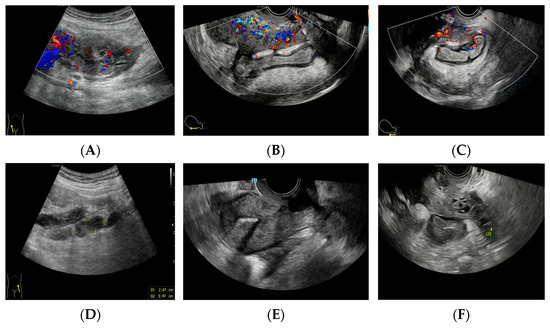

Figure 4. (A) A gradual reduction in the mass. (B) The eventual resolution of the mass, confirming a diagnosis of Actinomyces infection. Pelvic actinomycosis, a rare subacute to chronic granulomatous disease, constitutes approximately 3% of all actinomycosis cases [1]. Long-term IUD placement can lead to endometrial damage, facilitating the invasion of Actinomyces into the subendometrial layer. This invasion often extends to the fallopian tubes and ovaries, where Actinomyces secrete protein hydrolases that can exert a malignancy-like invasive effect and provoke an infection-like inflammatory response [2]. The clinical and imaging features of pelvic actinomycosis are not distinct, making its diagnosis challenging. Preoperative diagnosis is accurate in less than 10% of cases [3]. Although the imaging characteristics of pelvic actinomycosis are not unique, they also have some similar features with other diseases [2,4]. CT may reveal a thick-walled cystic or solid mass with heterogeneous enhancement. Ultrasound typically shows cystic–solid mixed echoes with abundant blood flow signals. In the early stages, the disease may present as an isolated mass. As the disease progresses, the mass enlarges, invading and compressing adjacent organs, and becomes increasingly irregular in shape and poorly demarcated from surrounding structures, complicating preoperative diagnosis. The affected intestinal wall may exhibit echogenic signs of inflammation due to invasion. The urinary tract can also demonstrate fluid dilatation due to compression and obstruction. On PET/CT, the mass often displays high fluorodeoxyglucose (FDG) uptake. Reflecting on this case, the localization of the lesion posed significant challenges. The copious inflammatory exudate and extensive adhesions within the pelvis obscured clear demarcation on tomographic images. Consequently, based on the patient’s prolonged gastrointestinal symptoms, both CT and PET-CT erroneously suggested an intestinal tract and mesentery origin. In contrast, ultrasonography, employing real-time scanning through various modalities and perspectives, accurately localized the lesion to the right adnexal region. Qualitatively, differentiating this disease from ovarian malignancy and pelvic tuberculosis is exceptionally challenging. Continuous differentiation throughout the course of the disease is imperative, especially considering the high failure rate (up to 50%) of Actinomyces cultures [1]. This necessitates extreme caution in postoperative pathological differentiation. Patients with ovarian cancer, predominantly older women, typically present with abdominal pain, distension, and cachexia, often lacking symptoms like chills and high fever. These cases are characterized by a marked elevation in CA125 levels. Unlike the extensive adhesions and sinus tract formation in the late stage of actinomycosis, larger ovarian tumors on imaging are often accompanied by significant abdominal or pelvic effusions and extensive lymphadenopathy. In this case, real-time dynamic ultrasound provided distinct advantages in determining the origin of the mass, assessing the extent of pelvic adhesions, and evaluating the involvement of surrounding tissues. It was also preferred for post-surgical efficacy assessment, playing a pivotal role throughout the diagnostic and treatment process.

Diagnostics 14 01923 g004